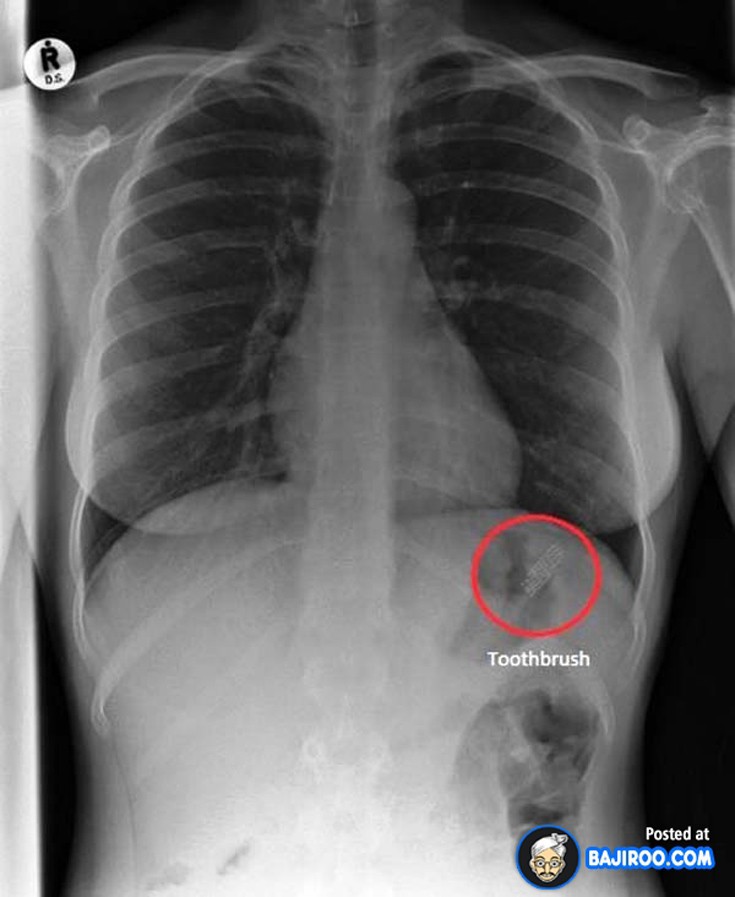

Ο,ΤΙ ΝΑ 'ΝΑΙ #ακτινογραφίες Παράξενα πράγματα που έχουν δείξει οι ακτινογραφίες Από δαχτυλίδια μέχρι πιρούνια και καρφιά - Δείτε τις φωτογραφίες 15·04·2016 11:08 1 σχόλια